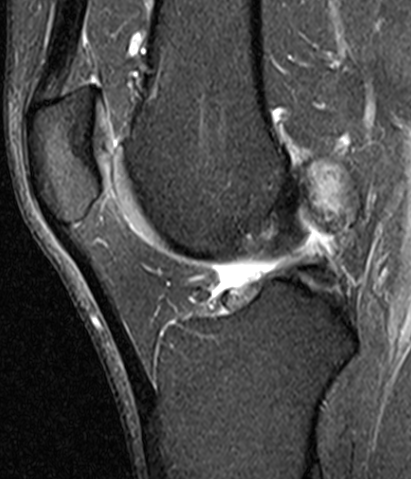

Diffuse

Severe diffuse PVNS with bony involvement